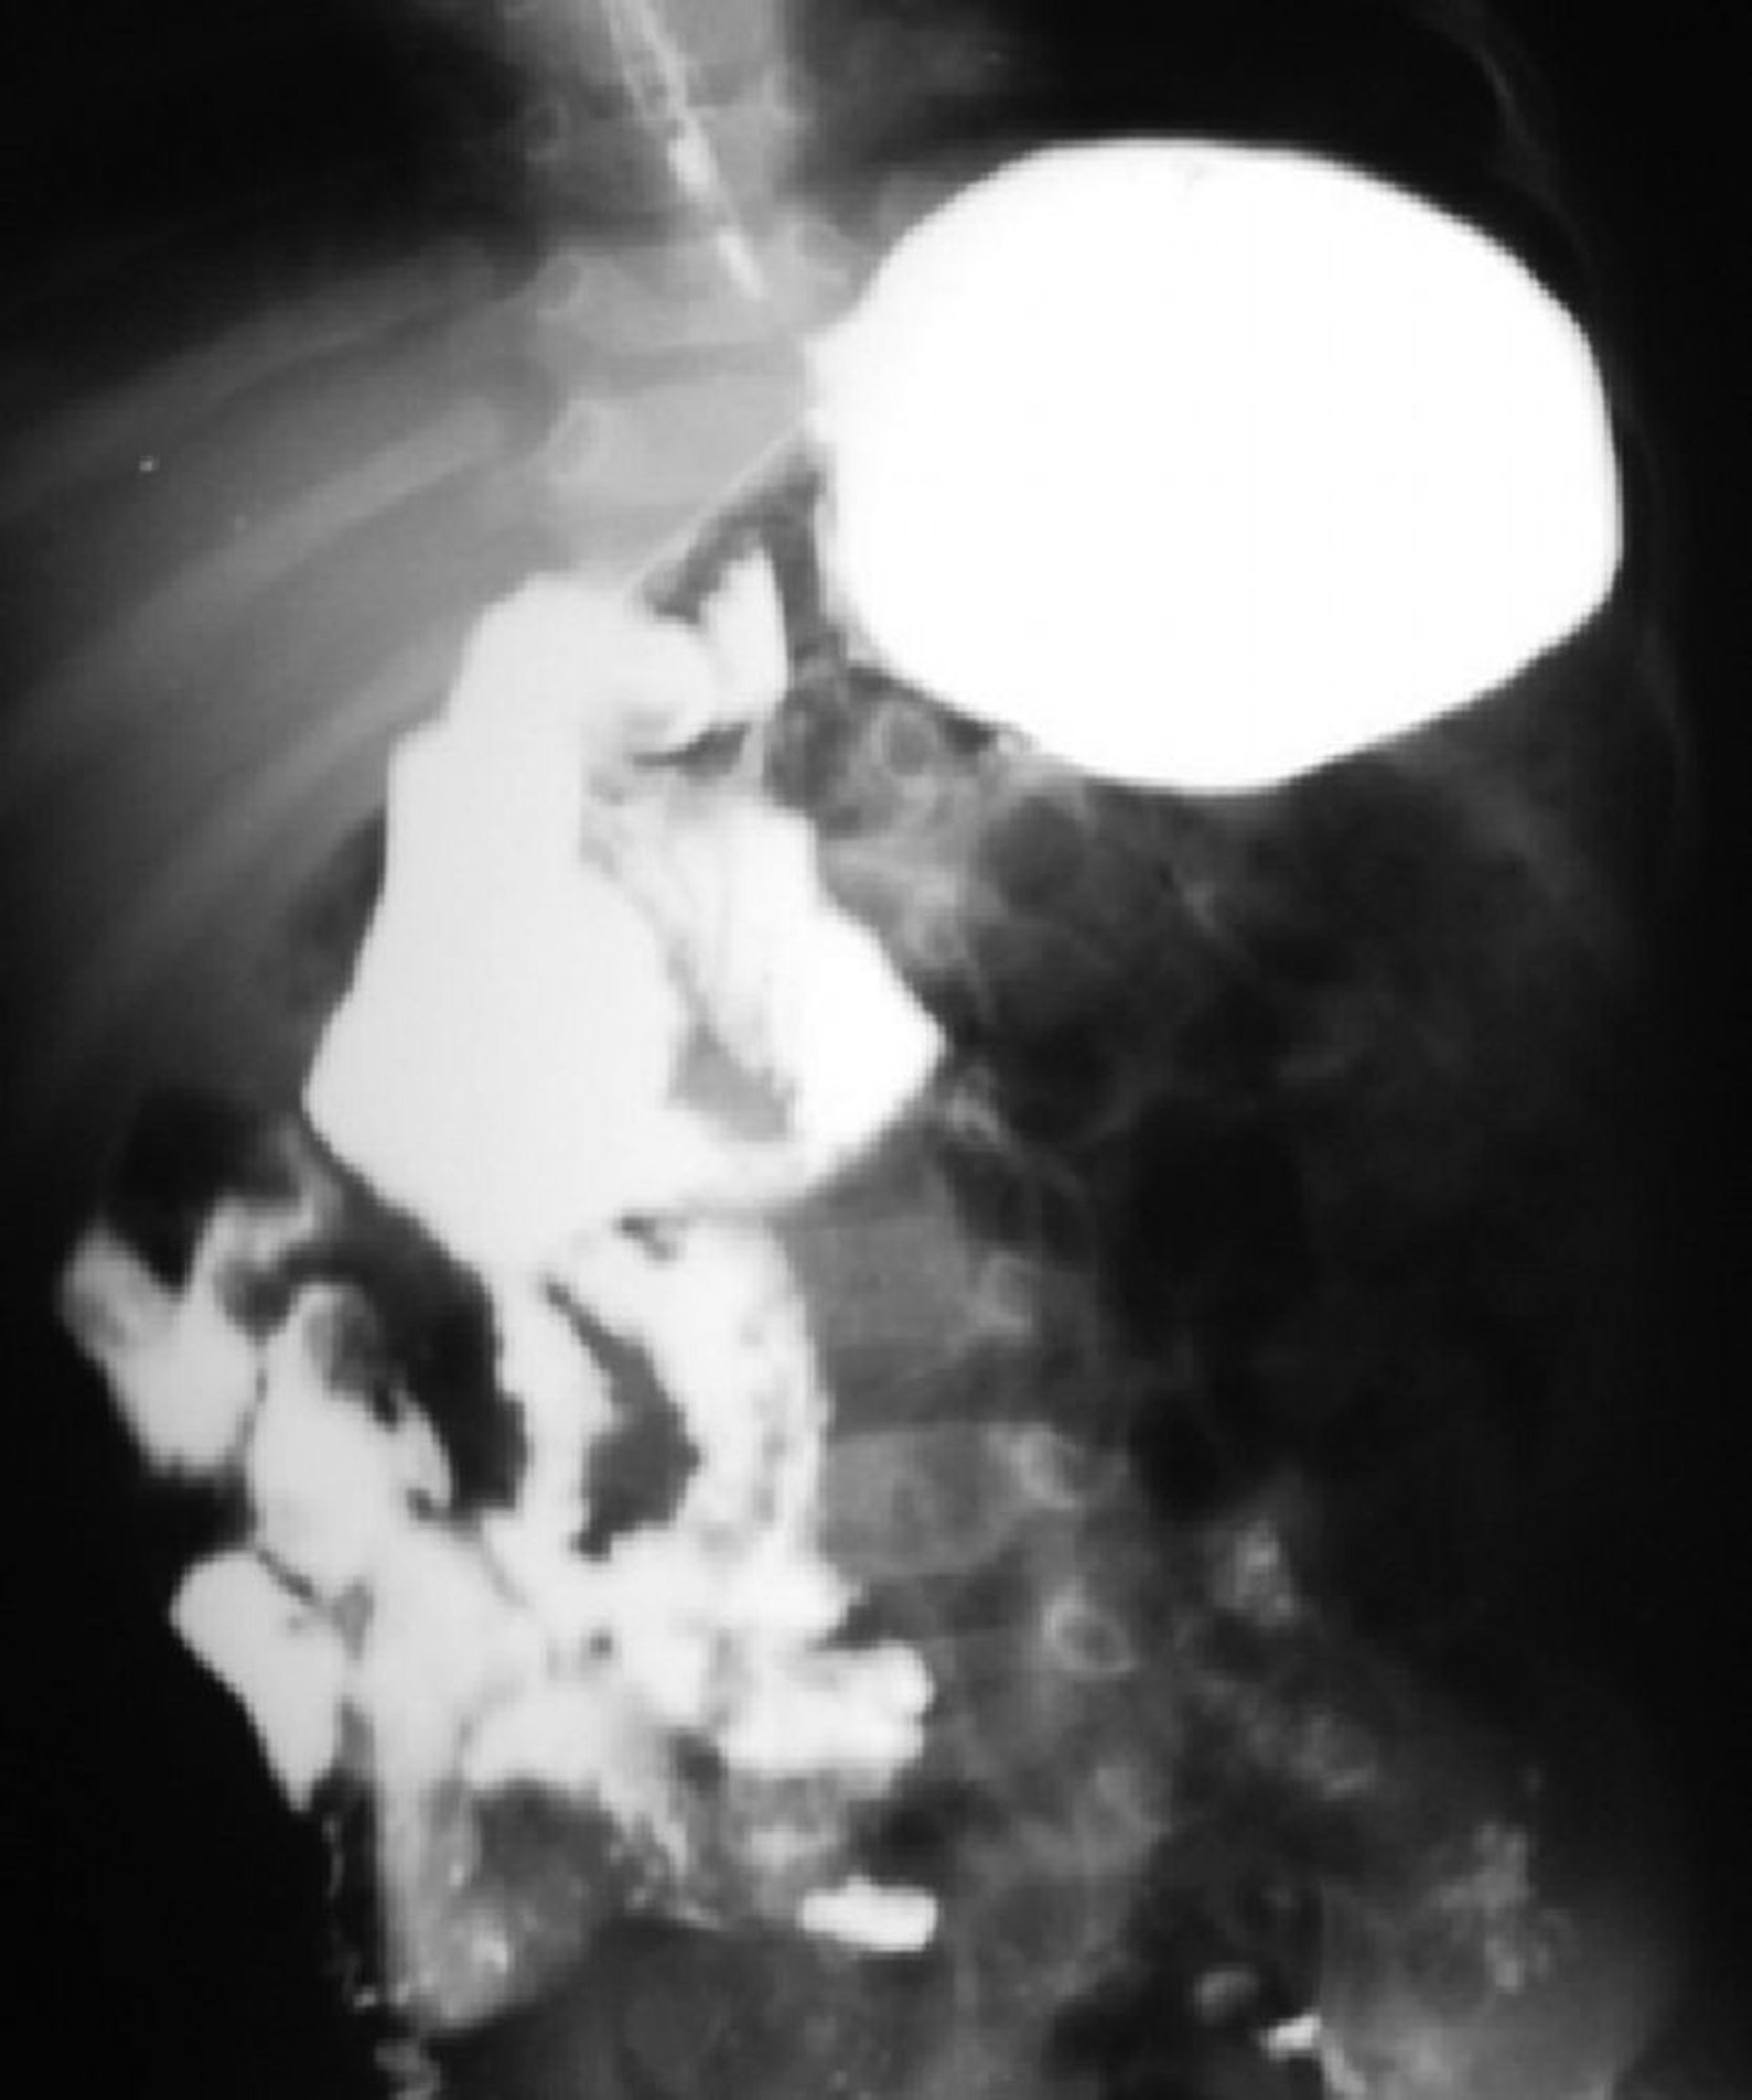

Diese Bariumuntersuchung zeigt eine Malrotation des Darms. Der duodenojejunale Übergang befindet sich auf der rechten Seite der Wirbelsäule, und der Großteil des Dünndarms liegt auf der rechten Seite.